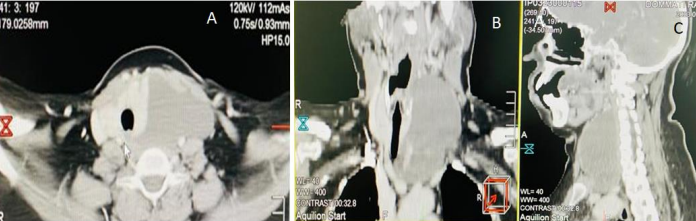

A High-resolution ultrasound revealed multiple hypoechoic nodules with micro-calcifications in the right lobe thyroid largest measuring 1.5*1 cm, TIRADS V, and another anechoic lesion adjacent to the left lobe of the thyroid. In addition, USG-guided FNAC suggested a Bethesda V lesion in the right lobe, and FNAC from the left lobe and cystic lesion were suggestive of colloid goitre. Because of the upper mediastinal extension of the lesion, a contrast-enhanced computed tomography of the neck and thorax was done, which was suggestive of a cystic mass measuring 10 × 7 × 8.5 cm adjacent to the left lobe thyroid displacing the left internal jugular vein and left common carotid. Along with nodular opacity and microcalcification in the right lobe thyroid. The superior and inferior extent from C3 cervical vertebrae to the aortic arch (Figure 1). Flexible laryngoscopy revealed no laryngeal or upper tracheal pathology except for the gross deviation of the laryngeal framework towards the right.

Figure 1: Depicts the Contrast enhanced computer tomography of the lesion